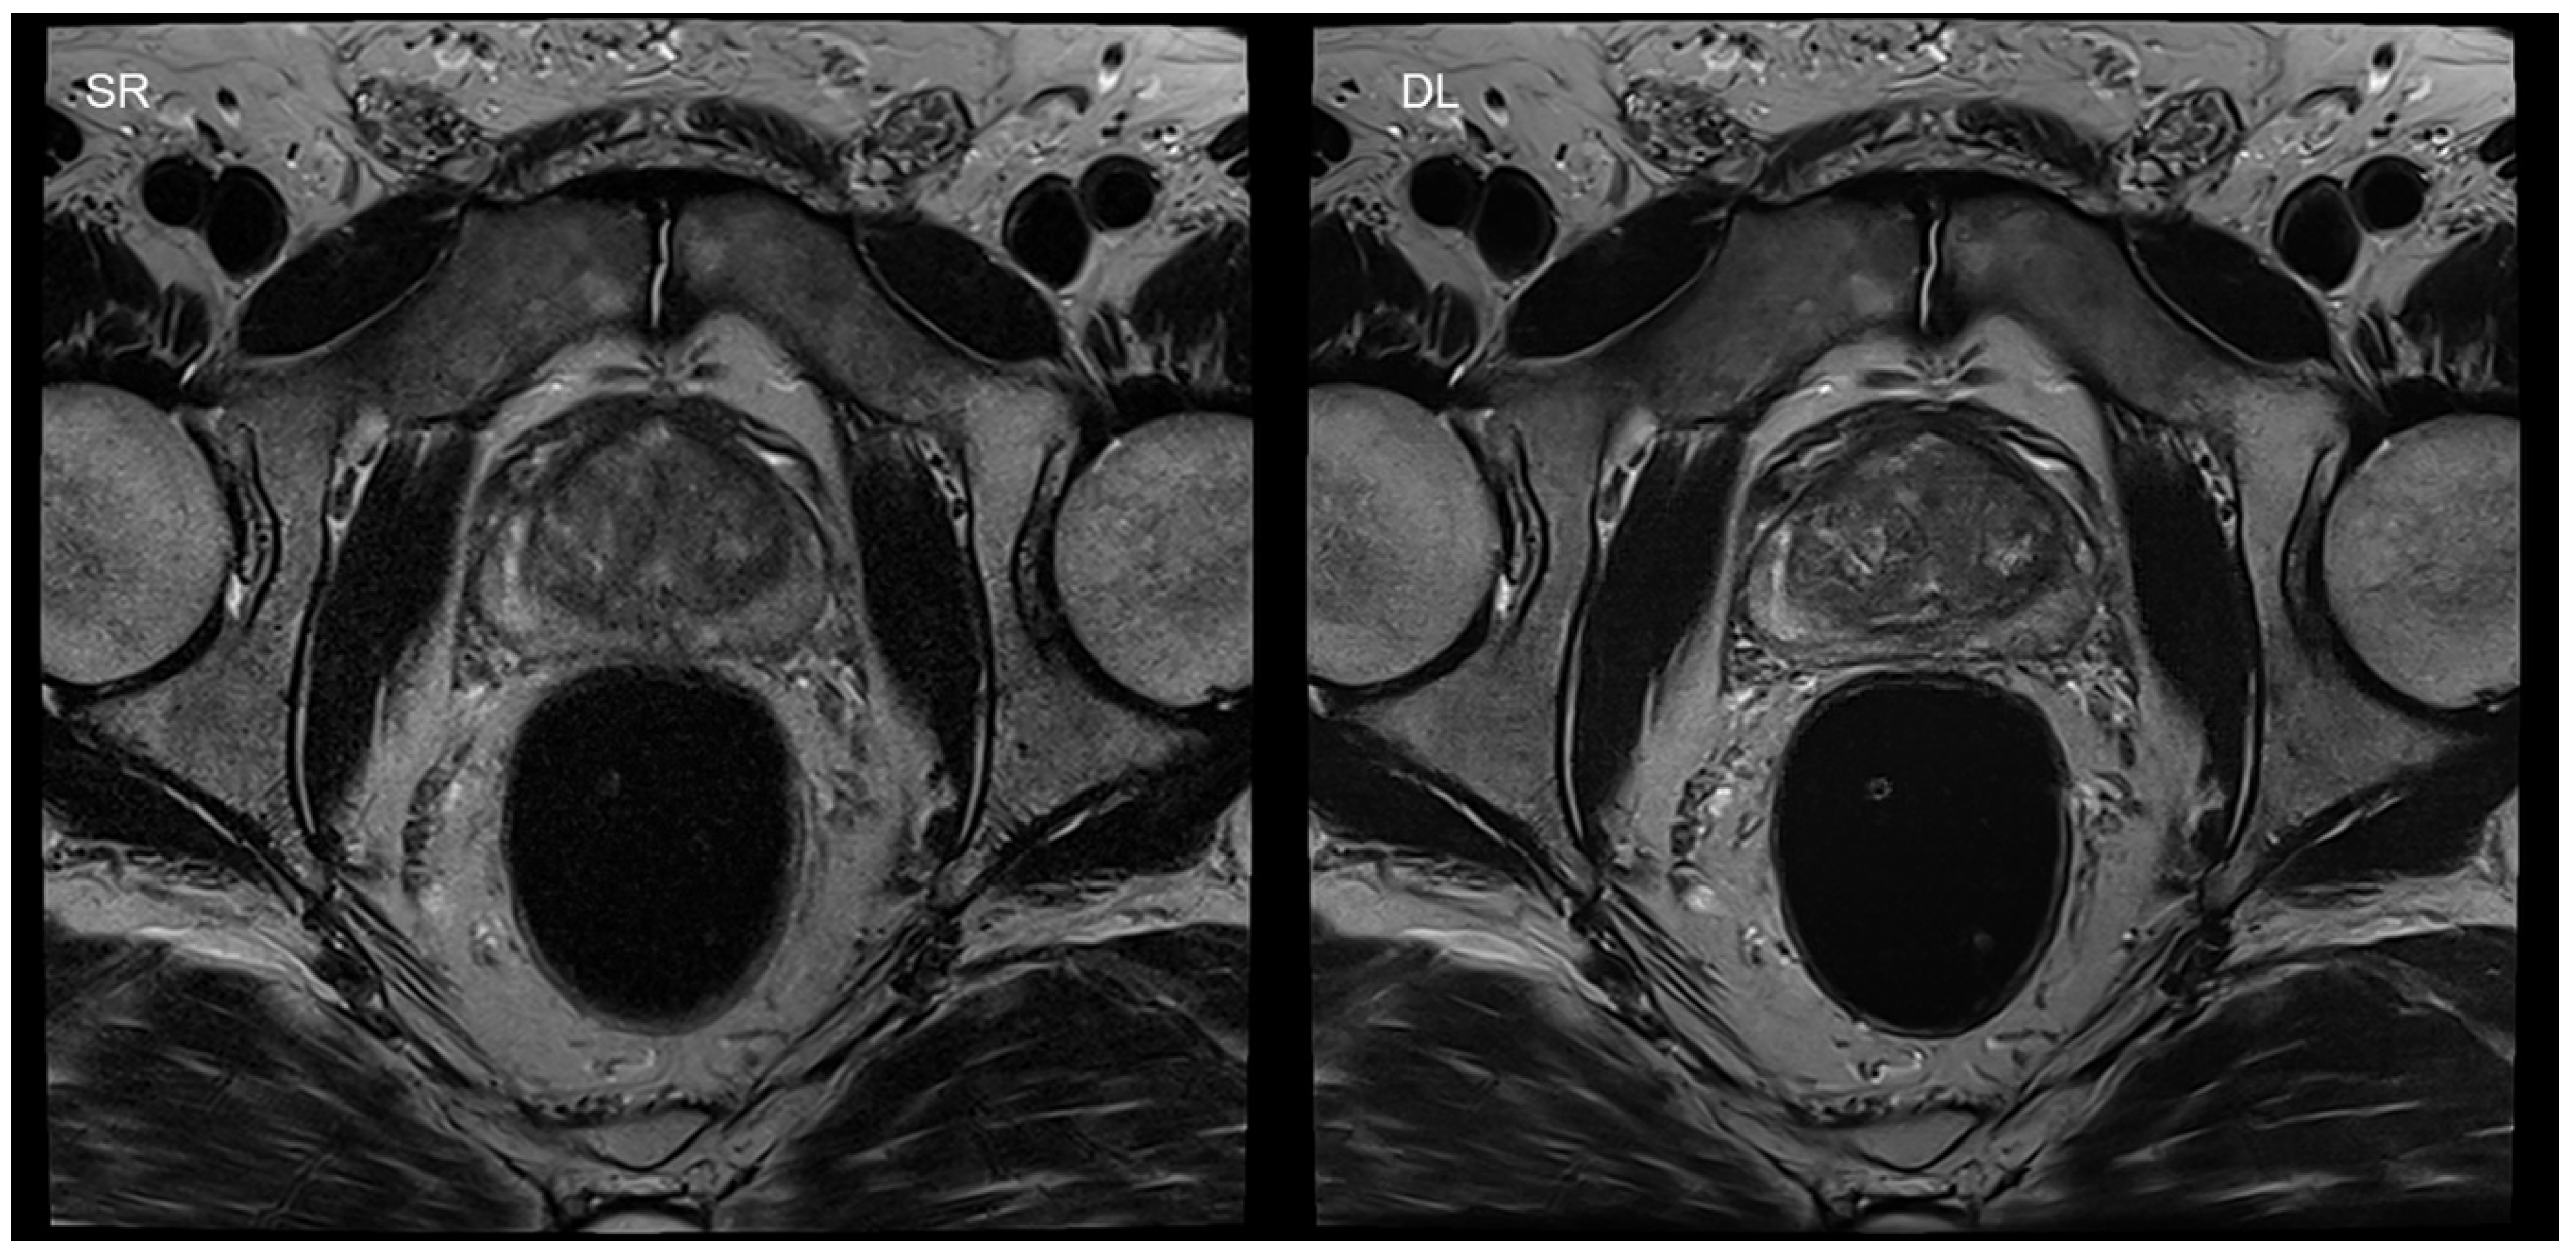

- Gassenmaier, S.; Afat, S.; Nickel, D.; Mostapha, M.; Herrmann, J.; Othman, A.E. Deep learning-accelerated T2-weighted imaging of the prostate: Reduction of acquisition time and improvement of image quality. Eur. J. Radiol. 2021, 137, 109600. [Google Scholar] [CrossRef] [PubMed]

- Gassenmaier, S.; Afat, S.; Nickel, M.D.; Mostapha, M.; Herrmann, J.; Almansour, H.; Nikolaou, K.; Othman, A.E. Accelerated T2-Weighted TSE Imaging of the Prostate Using Deep Learning Image Reconstruction: A Prospective Comparison with Standard T2-Weighted TSE Imaging. Cancers 2021, 13, 3593. [Google Scholar] [CrossRef]